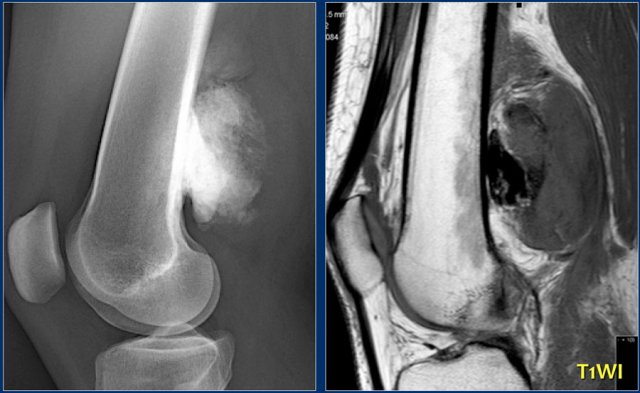

Study the images of a 14-year old boy and then continue reading.

The findings are:

• Radiograph.

Mixed lytic-sclerotic lesion in distal femur metaphysis and diaphysis with possible extension to the epiphysis.

The matrix of the tumor is bone.

Diagnosis: osteosarcoma.

• MRI.

Coronal image confirms the epiphyseal involvement with reactive edema.

Axial image shows the circumferential soft tissue extension and relationship to the neurovascular structures.